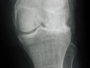

Jedes Gelenk ist eine funktionelle Einheit und besteht zusätzlich zur knöchernen Verbindung aus dem Gelenkknorpel, der Synovialmembran und der Gelenkflüssigkeit. Damit eine gleichmäßige Belastung auf das Gelenk trifft, verteilen Muskulatur und Gelenkkapsel die auftretenden Kräfte und unterstützen die Ernährung des Gelenkknorpels. Der Knorpel fängt die Kräfte auf und wirkt wie ein Stoßdämpfer und durch die glatte Oberfläche und die Synovialflüssigkeit wird ein reibungsloses Gleiten der Gelenkflächen aufeinander sichergestellt. mehr »